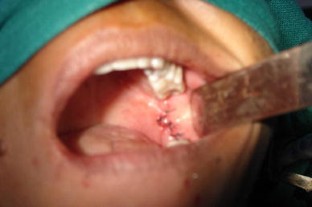

Fig. 2